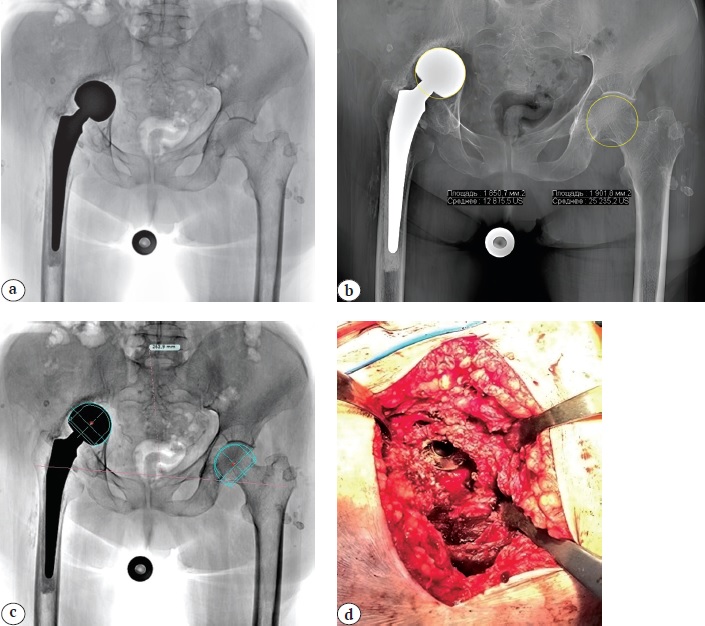

Рис. 4. Клинико-рентгенологическая картина тяжелой протрузии вертлужной впадины, развившейся у пациентки 81 года через 3 года после первичной гемиартропластики по поводу перелома шейки правой бедренной кости:

а — первичный обзорный рентгеновский снимок таза (определяется протрузия монополярного гемиэндопротеза); b — расчет площади окружности головки бедренной кости с левой здоровой стороны (19,0 см2), справа — площади окружности монополярной головки эндопротеза — 18,5 см2. Отмечается снижение данного параметра на 0,51 см2; c — данные предоперационного планирования, выполненного в программе TraumaCad 2.5.7. Размер головки гемиэндопротеза (46 мм) правого ТБС спроецирован на левую сторону. Отмечается недостаточная величина выбранного размера; d — дефект дна и крыши вертлужной впадины, на дне которой определяется монополярная головка гемипротеза

Figure 4. Clinical and radiographic picture of severe acetabular protrusion in an 81-year-old patient, developed 3 years after primary hemiarthroplasty for the fracture of the right femoral neck:

a — initial plain pelvic X-ray showing protrusion of the monopolar prosthesis; b — calculation of the femoral head circumference area: 19.0 cm2 on the healthy left side and 18.5 cm2 on the right side with the monopolar prosthesis, indicating a reduction of 0.51 cm2; c — preoperative planning using TraumaCad 2.5.7 software: hemiarthroplasty prosthesis head size (46 mm) from the right hip joint projected onto the left side demonstrates inadequate sizing of the chosen implant; d — defect of the acetabular floor and roof, with the monopolar prosthesis head positioned within the acetabular floor